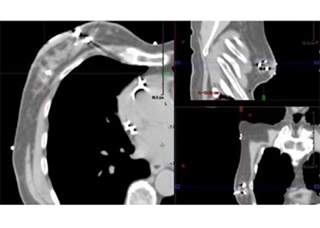

The Accusyte 3D Fiducial Marking System marks the planes of a soft tissue cavity after a tumor has been removed. The fiducial sutures are used when soft tissue needs to be marked for future medical procedures, such as subsequent radiation therapy.

After a biopsy or tumor removal, the Accusyte fiducial sutures are sewn around the perimeter of the tumor bed at the anterior, posterior, middle, and lateral planes of the tumor cavity. The fiducials allow for accurate delineation of target volumes during treatment planning and assist with image guided radiation therapy (IGRT) before each session.

The fiducial markers are woven within an absorbable suture. When the body absorbs the suture, the fiducial markers remain within the tissue. Migration of the markers from their original position is unlikely, as the tissue produced during the healing process holds the markers in place. Sutures are sewn into place using the same technique as other sutures commonly used.